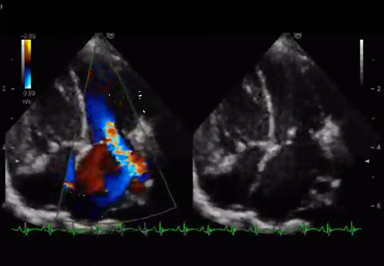

心臓超音波検査では,治療開始2週間で三尖弁逆流が軽減した.入院時TRPG=69 mmHgとoversystemic PHの状態あったが,徐々にTRPGが低下し,PHの改善が見られた.右室圧の低下に伴って左室は円形となり左室拡張末期径は,17.2 mmから21.0 mmに改善が得られた.左室扁平度は,入院時0.36,治療開始~退院時0.68,退院後フォロー時1.07と改善した8)

その後,MS・MRが改善し,入院1か月で,MRはmoderate,1か月半でmildまで改善した.MSに関してはtransmitral flowはE peak velocityが2.26 m/secから1.50 m/secまで低下し,Pressure half timeの延長も改善した.僧帽弁尖の肥厚や輝度上昇は変化がなかったが,coaptation depthは6.6 mmから2.1 mmまで改善し,coaptation heightも2.7 mmから5.5 mmまで改善した(Table 2, Fig. 3).

Pediatric Cardiology and Cardiac Surgery 34(4): 215-221 (2018)

Fig. 3 Mitral valve measurement in Table 2

準緊急的に手術待機としていたが,利尿剤およびジゴキシンの内服のみでMS・MRおよびPHの改善が得られ,呼吸・循環動態が安定したため,入院から約2か月で自宅退院が可能となった(Fig. 4, Movie 3).